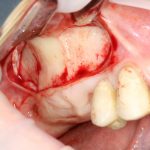

Простой синуслифтинг. Часть I.